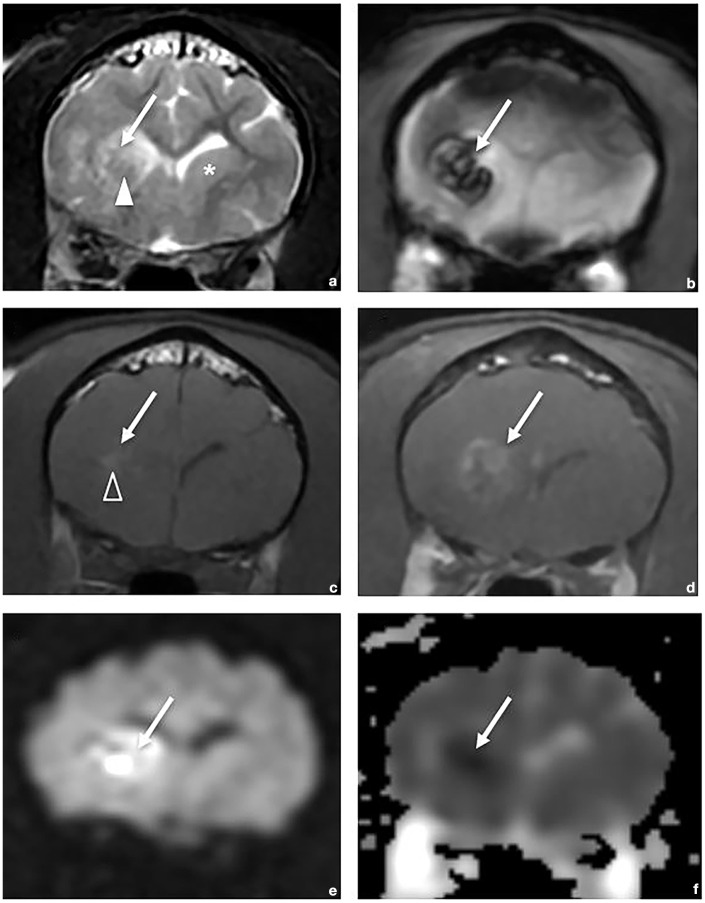

Clinical and MRI findings of hemorrhagic infarcts in two cats with positive outcomes.

Case series summary: A 1.5-year-old male neutered domestic shorthair cat presented with an acute onset of lethargy and difficulty jumping. Prior medical history included a restrictive perimembranous ventricular septal defect and mild mitral regurgitation. Neurologic examination showed left hemiparesis and absent menace in the left eye. MRI revealed a lesion in the right frontal lobe and caudate nucleus with intralesional hemorrhage and restricted diffusion consistent with hemorrhagic infarct. A 6-year-old male neutered domestic shorthair cat presented with three neurologic episodes over 3 months, one consisting of circling to the right, absent menace in the right eye and right-sided postural reaction deficits, and the other two consisting of vestibular signs. MRI revealed a chronic hemorrhagic infarct of the left caudate nucleus. Both cats demonstrated favorable recovery, with cat 2 experiencing a fourth event 9 months after MRI.

Relevance and novel information: This case series details the first two cases of feline hemorrhagic infarct with ante-mortem diagnosis, MRI findings and recovery with a good long-term outcome. Hemorrhagic infarcts, uncommonly reported in companion animals, are a subtype of stroke involving hemorrhage resulting from reperfusion or collateral circulation into an ischemic area of brain tissue. This report discusses typical MRI findings in humans, including differentiation from intracerebral hemorrhage, and the potential role of comorbidities on the development and outcome of hemorrhagic infarcts in cats.